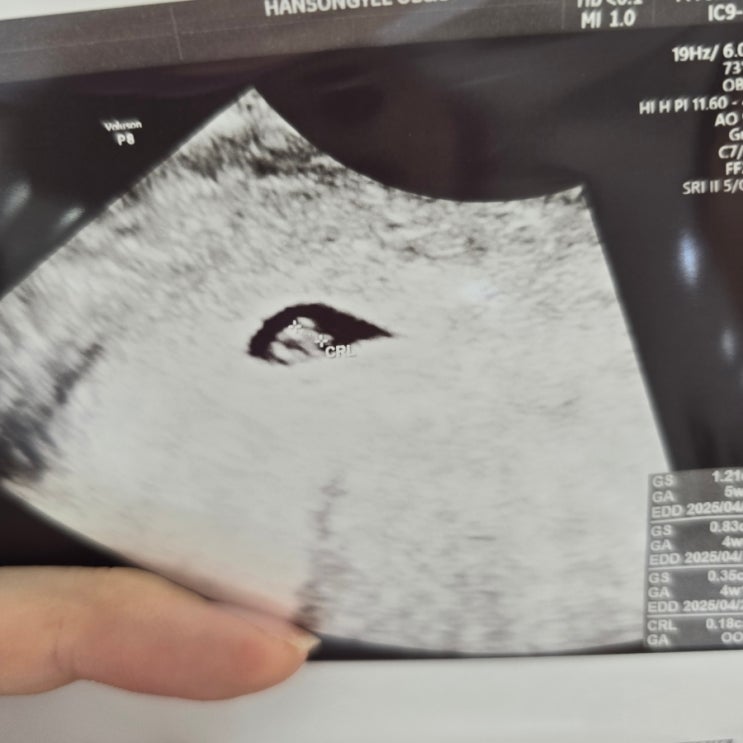

임신 7주차 아기집, 난황, 아기까지 확인했지만 심장깜빡임 없음. 계류유산과 소파술 그 이후

임신 7주차 계류유산, 소파술 후기 안녕하세요. 현두야현두입니다. 오늘은 다소 좋지 않은 소식으로 블로그...